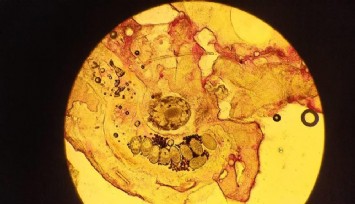

Doç. Dr. Kahraman, “TÜBİTAK tarafından destelenen projemiz ile akciğer kanseri tipleri içerisinde en fazla görülen tür olan küçük hücreli dışı akciğer kanseri hücrelerinde borik asidin antikanser etkilerini araştırmayı amaçladık. Bu amaçla akciğer kanseri hücrelerinde borik asidin kanser hücre canlılığını azaltma ve apoptotik hücre ölümünü indükleme yetenekleri üzerine olan etkileri incelenecek, ayrıca borik asidin kanser hücrelerinin koloni oluşturarak tümör formasyonu kapasitesi oluşturmasını önleyip önlemediği araştırılacaktır. Bununla birlikte kanser hücre morfolojisi, kanser hücre göçü ve metastazını üzerine etkileri de ortaya konacaktır. Bu analizlerin yanında in vitroda 3 boyutlu kültür ortamında akciğer kanseri tümör sferoidleri üretilecek ve borik asidin akciğer kanseri tümörünün büyümesine, yapısına, morfolojisine ve bütünlüğüne olan etkileri de gösterilecektir. Projemiz ile elde edecek olduğumuz bilgiler, borik asidin akciğer kanserinde temel hücresel antikanser mekanizmalar üzerine olan etkilerini ortaya koyacak ve bor içeren hedefli yeni tedavi modellerinin oluşturulması için kaynak veriler sağlayacaktır. Ayrıca verilerimiz, Türkiye için stratejik bir öneme sahip olan bor madenlerinin kanser tedavisinde umut vadeden bir molekül olup olmadığını ortaya koyacak ve bu stratejik madenlerin daha da önem kazanmasına katkı sağlayacaktır” diye konuştu.